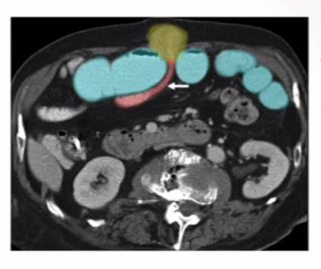

Etiology of this SBO?

The arrow showing a rapid transition point btwn dilated (proximal) and collapsed (distal) bowel

-w/ no other etiology this is diagnostic for SBO 2/2 adhesion